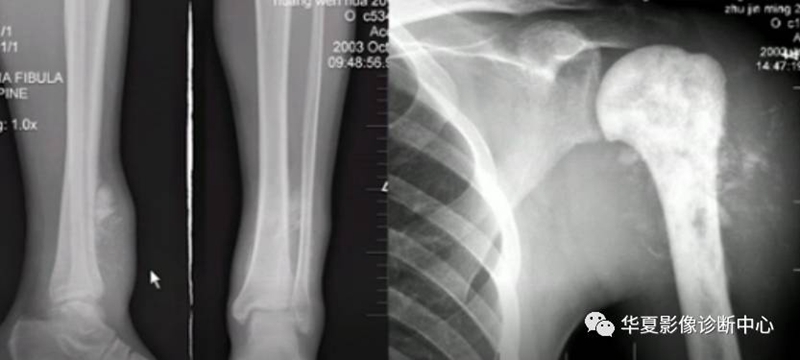

3、肿瘤骨形成

象牙样:密度很高,境界不清,无骨结构。

絮状:密度较高,境界模糊,无骨结构。

针状:垂直骨体,排列紧密,针状影。

骨质增生,骨膜反应,良性者边续,局限,清楚,厚在2mm以上,恶性者间断,相对广泛。

骨样骨瘤良性骨膜反应,骨肉瘤恶性骨膜反应